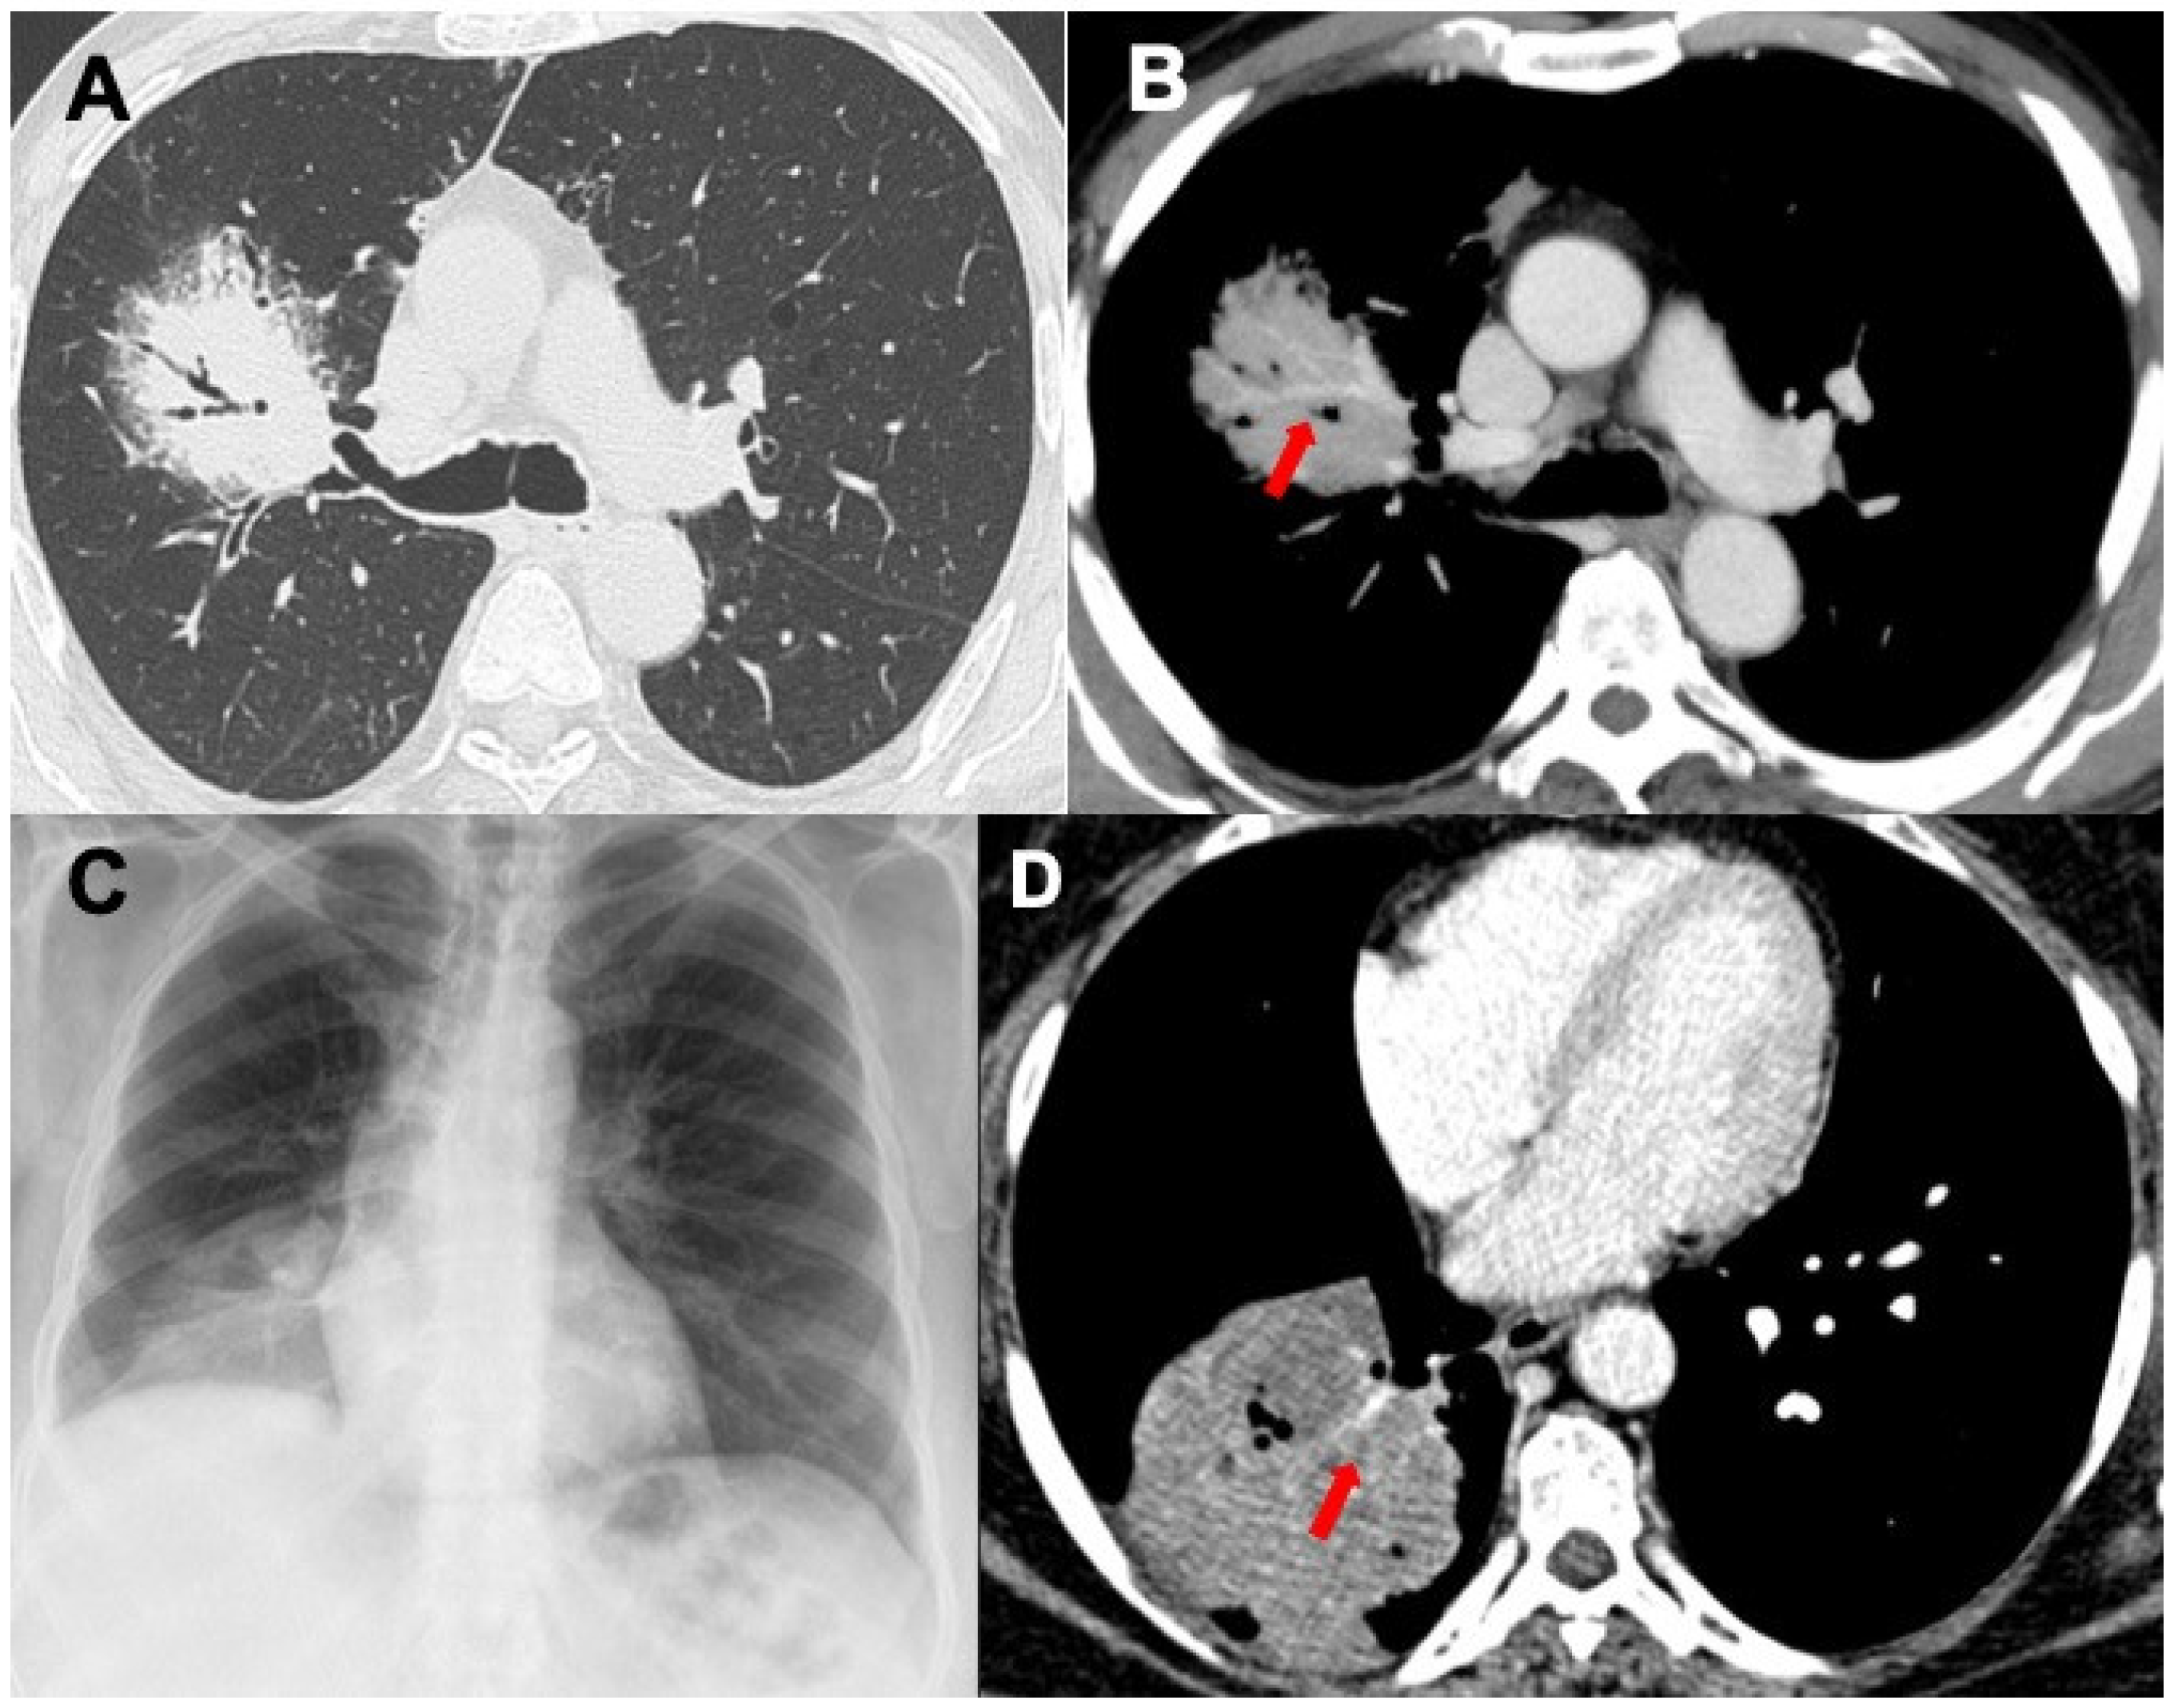

3.1. Consolidations

3.2. Nodules and Masses

| MALT | Consolidations, bronchovascular distribution without topographic predominance, lobar-like pneumonia (rare), ±bulging fissure sign, ±angiogram sign, ±air bronchogram; less frequently nodules, masses and GGO; interstitial involvement (very rare) | Neoplasms, lobar or focal atelectasis, infections (Klebsiella pneumoniae), OP, LIP, NLH, sarcoidosis |

| DLBCL | Masses and nodules, mediastinal nodes enlargement, GGO | Neoplasms, LYG, metastasis |